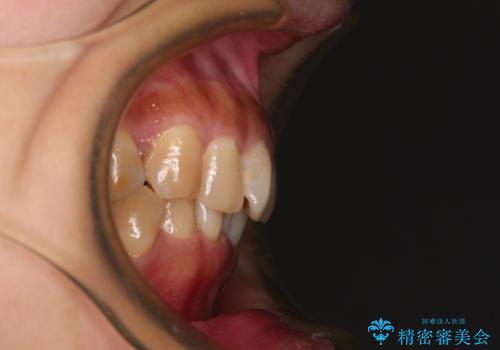

ディープバイトと前歯のデコボコ インビザラインによる矯正治療

- 前歯のディープバイトと叢生を気にして来院された患者様です。

目立ちにくい装置を希望されていたため、ワイヤー装置とインビザラインを提案したところ、インビザラインを希望されました。

下顎大臼歯が手前に倒れていたため、起き上がらせることで咬み合わせ高さを挙上し、ディープバイトと叢生を改善することとしました。